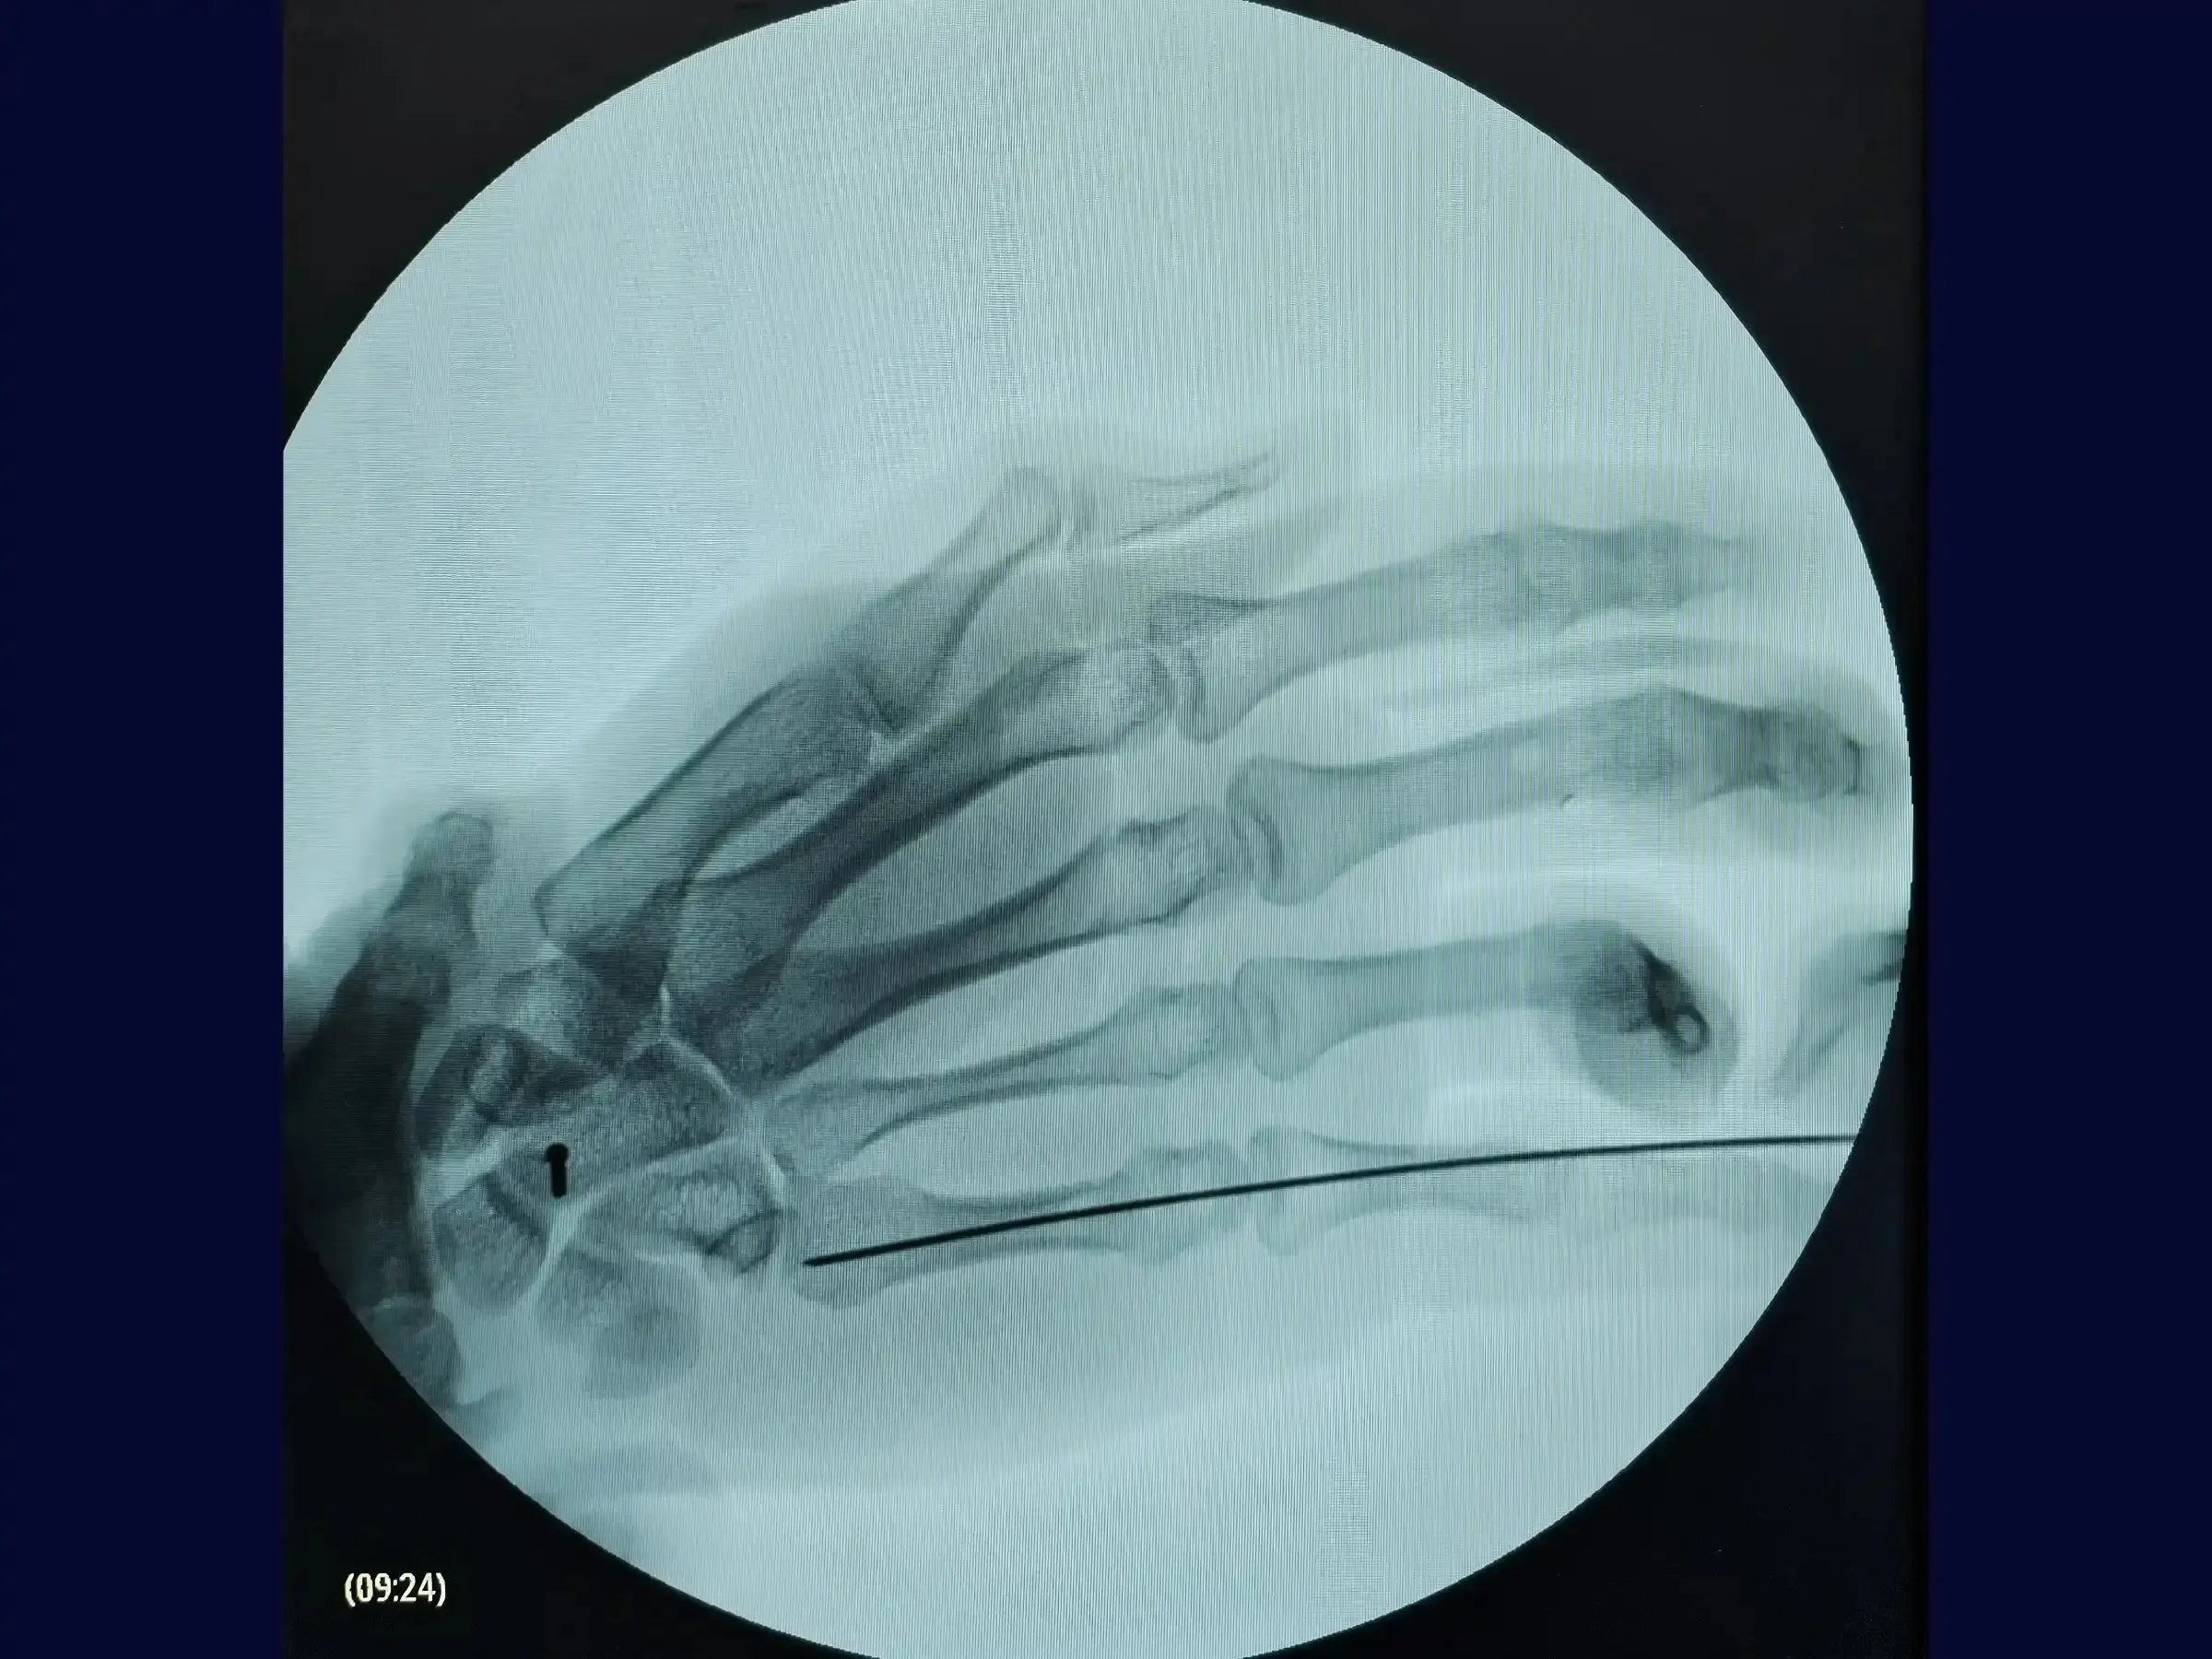

- Inserción optimizada de la guía: aprenda a insertar la guía según las marcas preoperatorias, garantizando una alineación precisa en las proyecciones anteroposterior, lateral y oblicua.

- Medición y perforación dirigida: aprenda a medir con precisión para determinar el tamaño de tornillo adecuado después de confirmar la colocación del alambre guía y perforar directamente sobre el alambre guía.